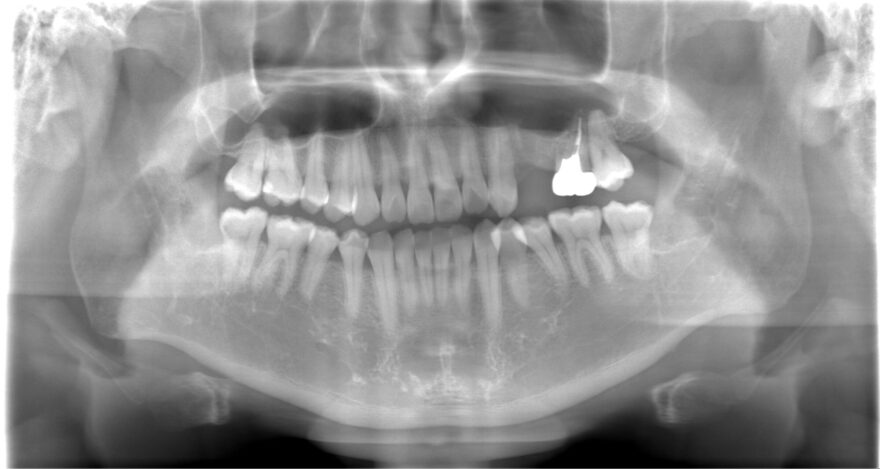

治療前のレントゲン写真

両サイドに2本のインプラントを埋め込み、3本の上部構造を支えるインプラントブリッジを患者様に提案しました。

埋め込むインプラントを3本ではなく2本にすることで、オペ後の腫れと痛みを少なく、治療費も少なくできます。